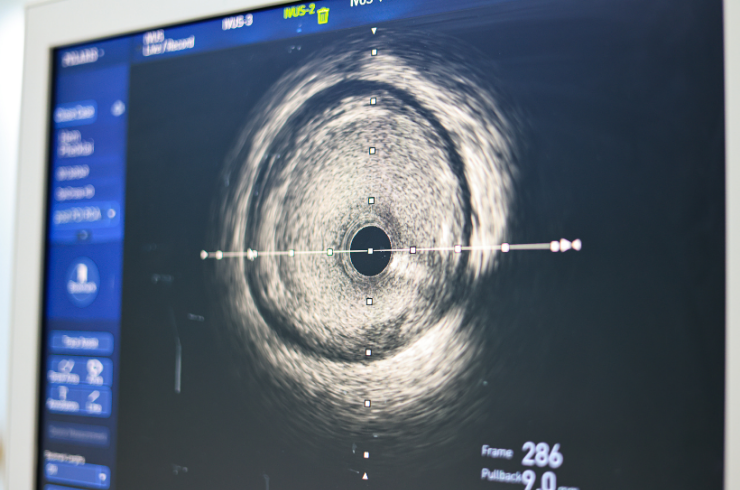

Advanced imaging techniques used to visualize coronary arteries internally for precise diagnosis and guided treatment.